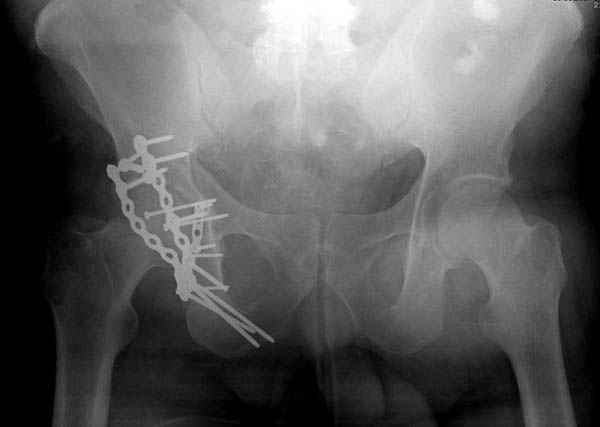

Второй случай, для лечения перелома проксимального

плеча применили пластину "Hand Innovation"

http://www.handinnovations.com/pdf/S3_technique.pdf

Пластина имеет преимущества перед другими "Locking

Implants", потому что пластину можно уложить намного ниже чем другие пластины и имеется возможности проведения шурупов под 130 градусным углом, таким образом можно уменьшить операционный разрез в проксимальной части.

Прооперирован вчера на 13 день после поступления.

Больному 41 и из-за гемодинамической нестабильности в течение первых 7 дней был в реанимации под интубационной седацией.

Кроме перелома плеча у больного старый дистракционный перелом T12-L1 оперированный когда-то и кем-то, открытый перелом костей предплечья, который был прооперирован в ночь поступления, после I&D (хирургической обработки). Из-за разрыва селезенки при поступлении травма хирургами произведено удаление.

Дополнительно имеется перелом ацетабулума: задняя

колонна с полупоперечным переломом, и переломы костей лица.

На седьмой день зафиксирован перелом ацетабулума через задний доступ. Перед операцией для профилактики DVT, IVC фильтер, также получает Lovenox.

Очень хорошаая работа, поздравляю! Хотелось бы увидеть снимок таза до операции. Каким образом и как долго предполагаете разгружать тазобедреннй сустав в дальнейшшем?

Отправитель: Evgueny Tchekashkine 30 Ноябрь 2007, 16:57

По снимку создается впечатление о высоком поперечном переломе, задней колонны, стенки; почему не пользовались *magic screw*?

Там множество обычных 2.7 мм шурупов, потом идет фиксация основными пластинами.

Полную нагрузку разрешаем в 12 недели, хотя движения в суставе с первых дней.

Снимки здесь....